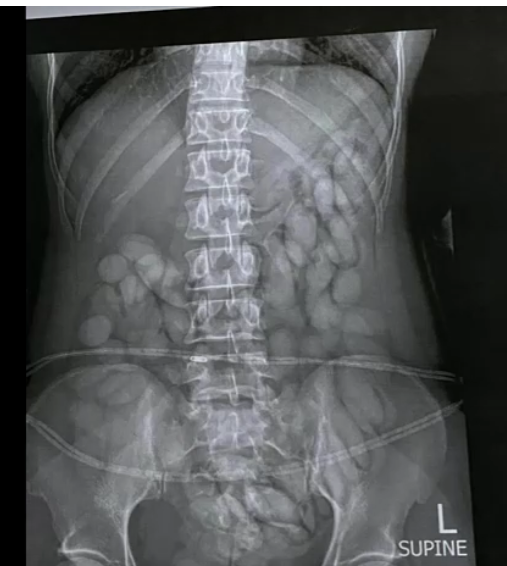

Sở Cảnh sát Nam Phi (SAPS) vừa công bố một đoạn video cho thấy những viên có thể là cocaine lấy từ cơ thể của một người vận chuyển ma túy tại Phi trường OR Tambo ở Johannesburg hôm Chủ Nhật, 22 tháng 9. SAPS cho biết đã bắt giữ một phụ nữ 30 tuổi, giữ hơn 63 viên thuốc nghi là cocaine nhưng cảnh sát vẫn chưa thể xác định giá trị của số ma túy bị tịch thu. Cảnh sát cũng công bố một hình ảnh chụp X-quang phát hiện ra vật thể lạ trong dạ dày của cá nhân bị bắt. Tuyên bố của SAPS cho biết nghi can là người Namibia và bà ta đã đến Nam Phi từ thành phố Sao Paolo của Brazil.